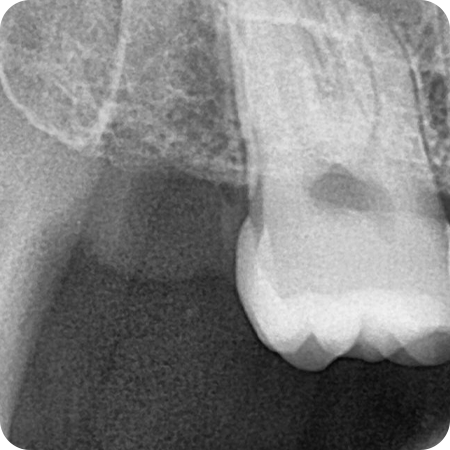

CASE 02

치경부마모 레진 치료

치경부 굴곡 파절과 마모가 있었고

예전에 때웠던 재료 탈락으로 시림 증상과

심미적인 개선을 함께 원하셨던 환자분

이차 우식 치료 후 레진 충전을 통해

심미적인 부분과 시림 증상까지 해소해 드렸습니다.

치료기간 : 2020.09.09 ~ 2020.10.06